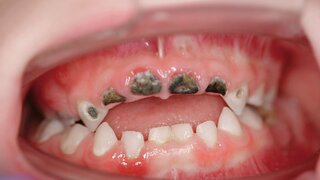

KindeswohlgefährdungIst frühkindliche Karies gleich Kindeswohlgefährdung? Frühkindliche Karies ist fast automatisch Dental Neglect, also Kindeswohlgefährdung. Das ist für die zahnärztliche Praxis relevant. Ausgabe 5/2024TitelKinderzahnheilkunde